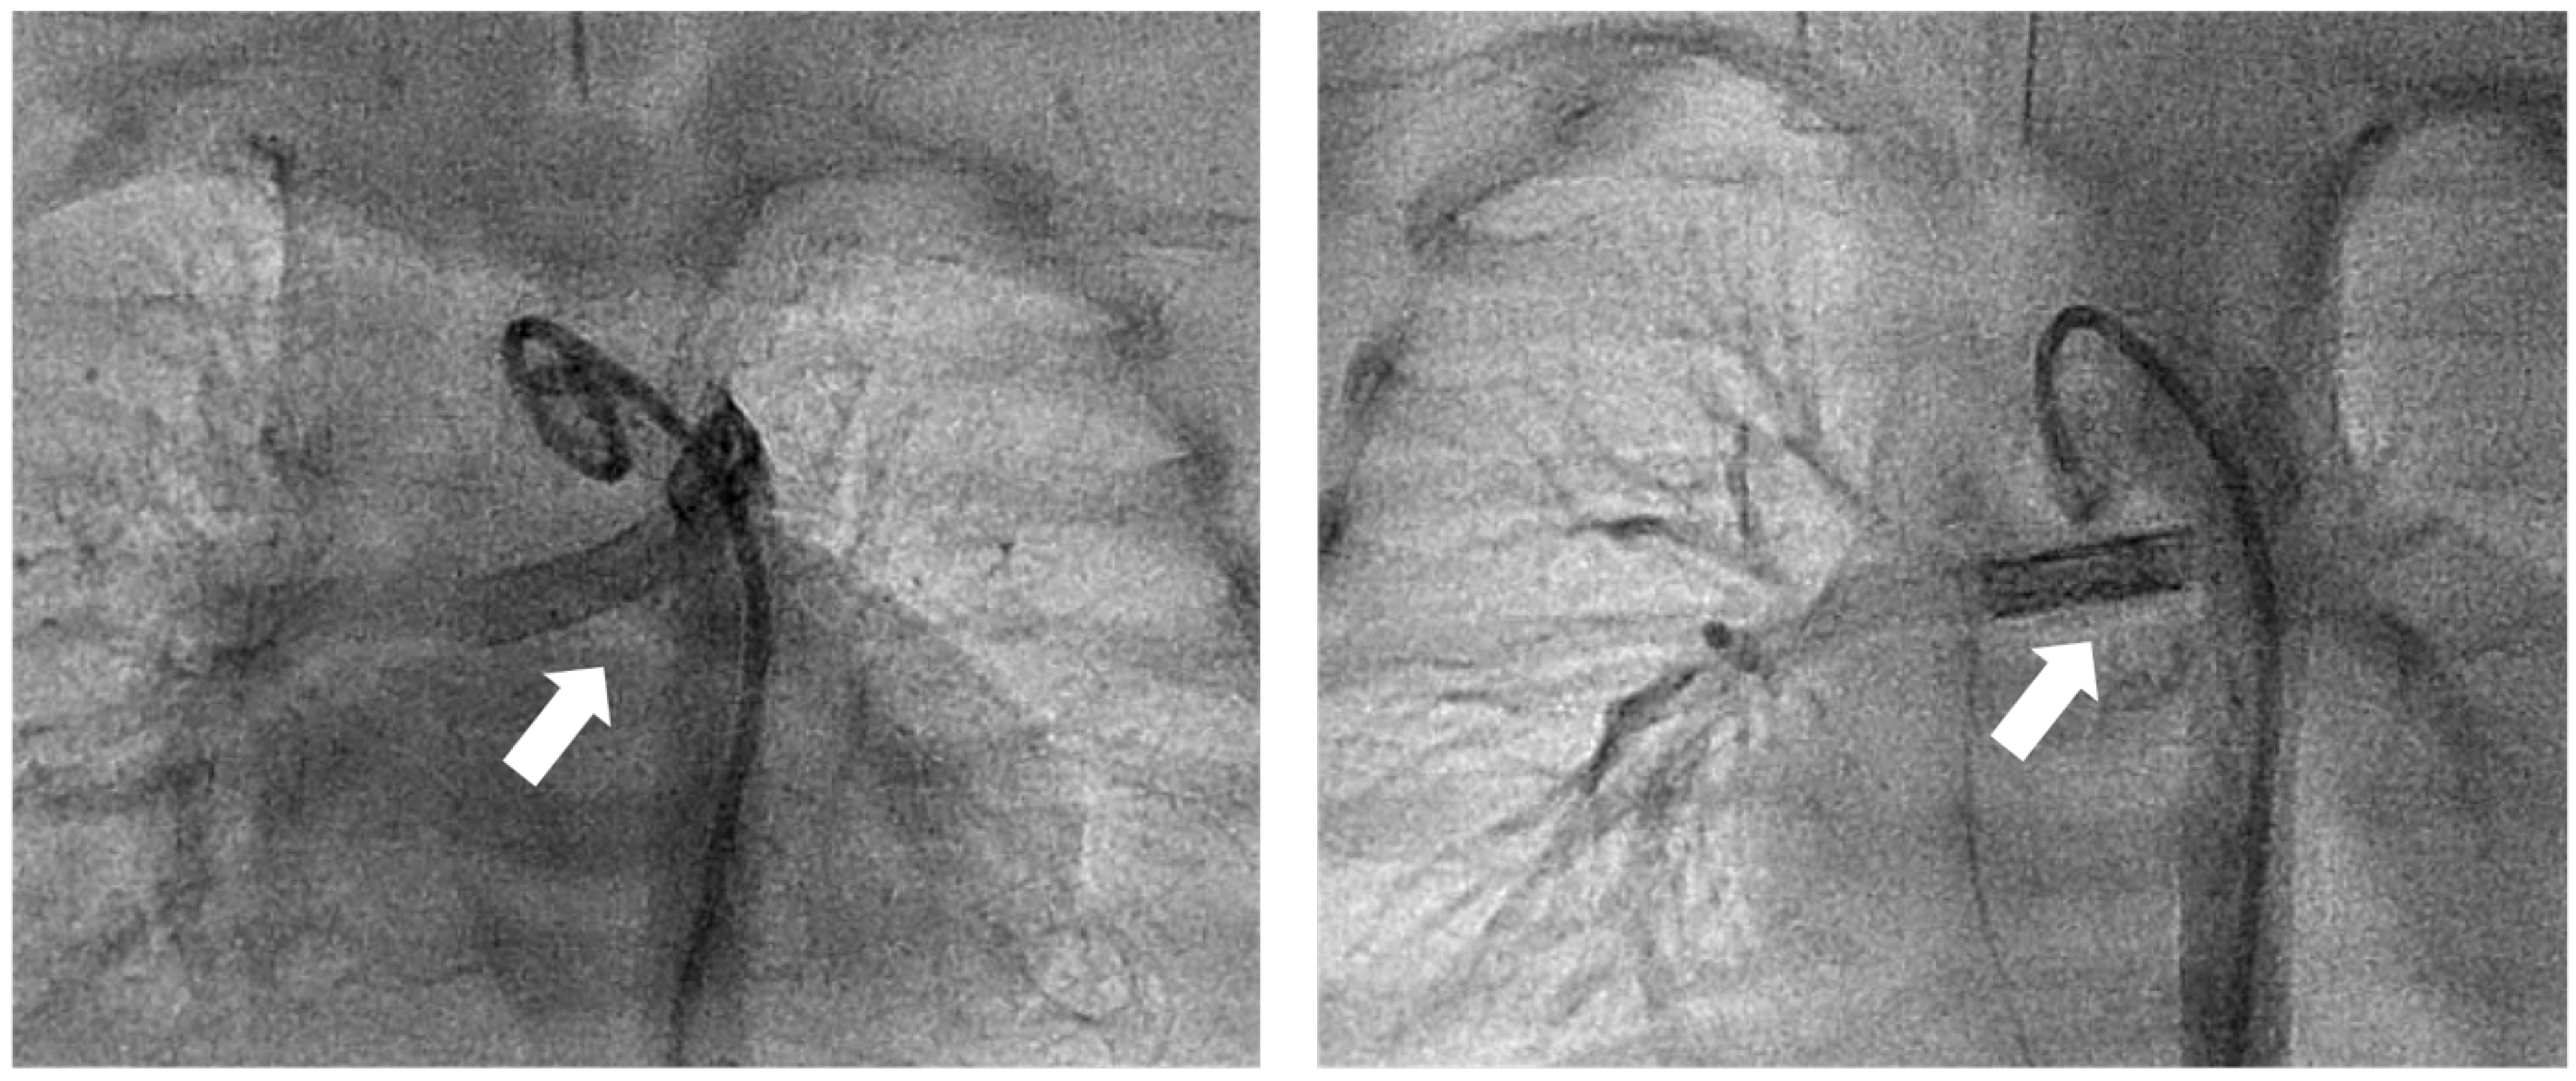

Figure 2.

Downsizing of PDA stent. Frontal view, angiography of aortic arch showing stented PDA (white arrow) after birth at day 4 (left) and after re-intervention at day 17 (right). At day 4 (left), two coronary stents (Multi-Link Vision®, 3.5 mm diameter) were implanted. At day 17, according to a mismatch of pulmonary hyperperfusion, with clinical signs of necrotising enterocolitis, five further coronary stents were implanted, reducing the PDA stent diameter from 3.3 to 2.8 mm.